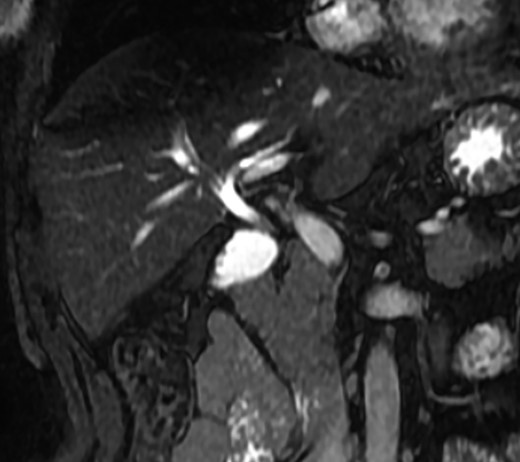

A magnetic resonance cholangiopancreatography (MRCP) confirmed the absence of gallbladder and of the cystic duct and artery (Figs 4–6). No other abdominal anomaly was identified.

MRCP coronal image showing the intrahepatic biliary tract, with good vision of common bile duct, right and left hepatic ducts and anterior branch duct.